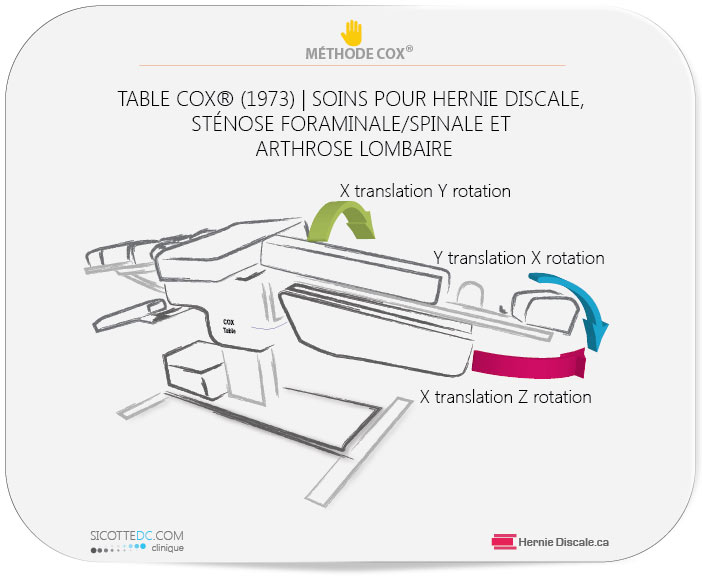

Avec la méthode Cox®, un patient peut percevoir une amélioration de 50 % en trente jours. L’ultime but est d’améliorer l’état du patient de 80 % à 100 %. Certains états d’usure vertébrale ou de hernie discale doivent percevoir 80 % comme un résultat satisfaisant.

Si le patient a complété une période de soins en flexion distraction Cox® sans amélioration, ou si une détérioration de la situation est évidente, une consultation externe sera nécessaire. Certains cas de sténose foraminale nécessitent absolument une injection pour accélérer la résorption et diminuer les symptômes. Ultérieurement, lorsque la douleur sera moins intense, le patient pourra reprendre les soins. Cette situation est peu fréquente.

COMMENT UN FORAMEN PEUT ÊTRE DÉCOMPRESSÉ

Pour la plupart des gens, les symptômes de compression ou de sténose foraminale disparaissent. Il n’y a aucun effet secondaire permanent à recevoir des soins en décompression, flexion et distraction Cox®. Par contre, les injections comportent plusieurs risques et ne font pas état de résultats convaincants (voir tableau de révision systématique de 350 recherches sur le sujet). La hernie discale réagit favorablement à une solution mécanique de décompression. Lors d’un soin Cox®, le trou de conjugaison augmente jusqu’à 28 % de sa grandeur originale (voir Neuf bienfaits de la méthode Cox®). Ceci permet au nerf de transmettre l’influx nerveux et diminue les symptômes de hernie discale.